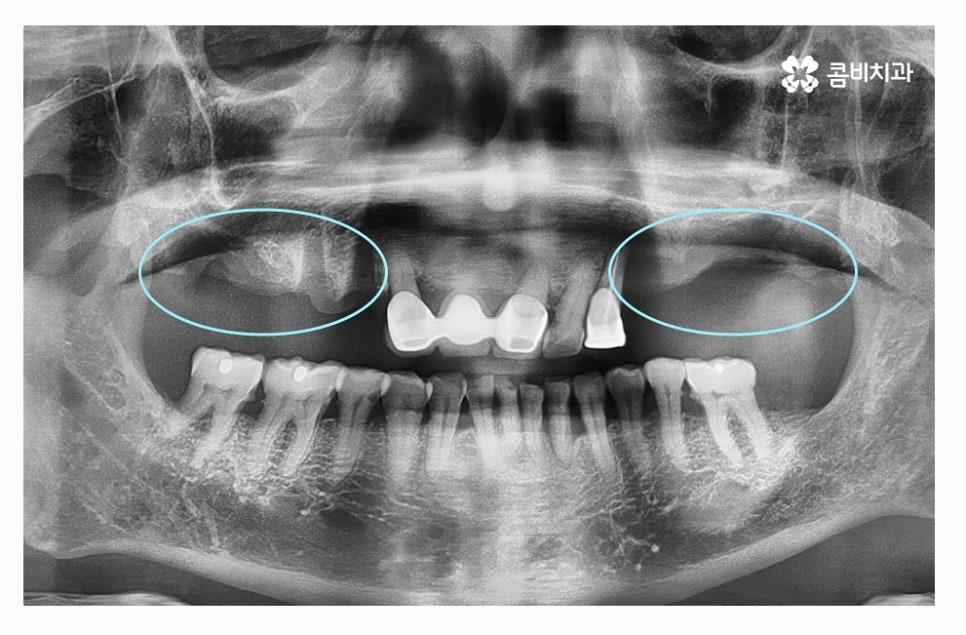

치아를 발치한 후 잇몸 뼈의 상태를 보면 잇몸이 내려앉아 있고

잇몸 뼈가 부족해진 상태라는 것을 알 수 있는데요.

전체임플란트를 해야 할 때 주의사항은 잇몸을 최대한 보존하고

임플란트를 한꺼번에 식립해야 하기 때문에 3D CT 등을 활용한

정밀검진부터 철저하게 해야 하고 식립 각도 하나하나에

철저해야 하기 때문에 의료진의 경험과 실력이 중요한 시술이라 할 수 있어요.